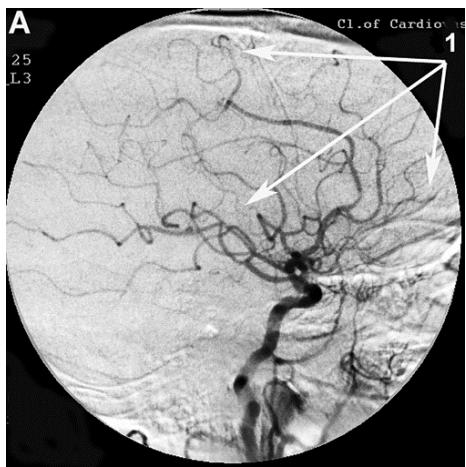

After transcatheter intracerebral laser PBMT, according to digital MUGA, all 48 (100%) patients showed a direct positive result manifested in pronounced angiogenesis, collateral and capillary revascularization, reduction of arteriovenous shunts, as well as an improvement in venous outflow (Figures 1A, 1B, Figures 2A, 2B).

Figure 2: Patient P., 75 years old, female. Medical history of AD - 12 years, TDR-3.

A. Left internal carotid artery angiogram, arterial phase, before transcatheter Intracerebral laser PBMT: 1. hypovascular areas in temporal and frontoparietal regions; B. Left internal carotid artery angiogram, arterial phase, after transcatheter Intracerebral laser PBMT: 2. stimulation of angiogenesis, restoration of collateral and capillary blood supply in the temporal and frontoparietal regions.